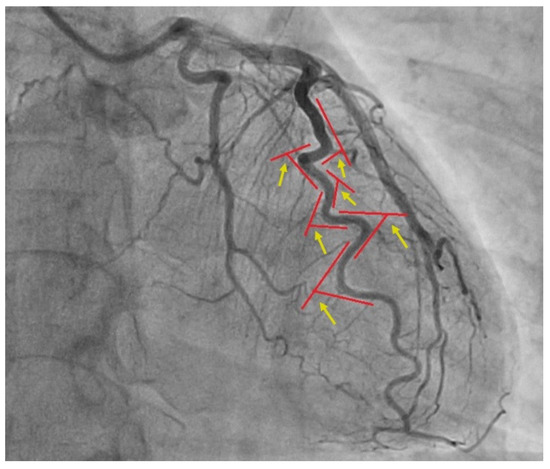

2. Materials and Methods